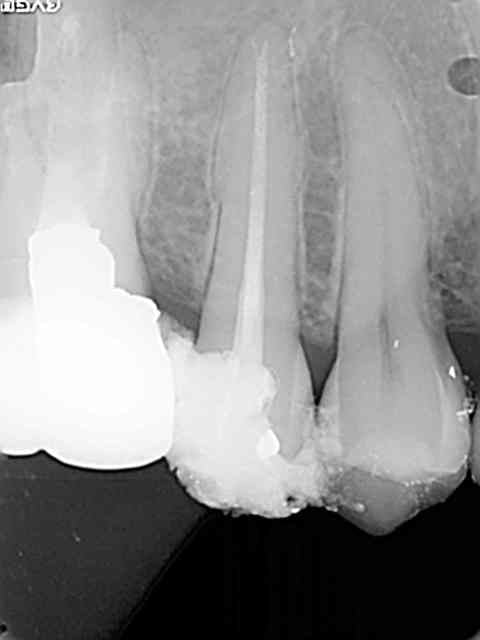

...avec même une petite touche égyptienne sur la première qui aurait fait plaisir à qui vous savez.

Une petite de ce matin et une plus ancienne, toutes les deux avec la même "recette".

Vous remarquerez en zoomant sur celle de ce matin comme le matériau a bien "squirté" en mésial. Devant de tels résultats, je ne vois pas pourquoi j'irai m'emmerder avec un system B...